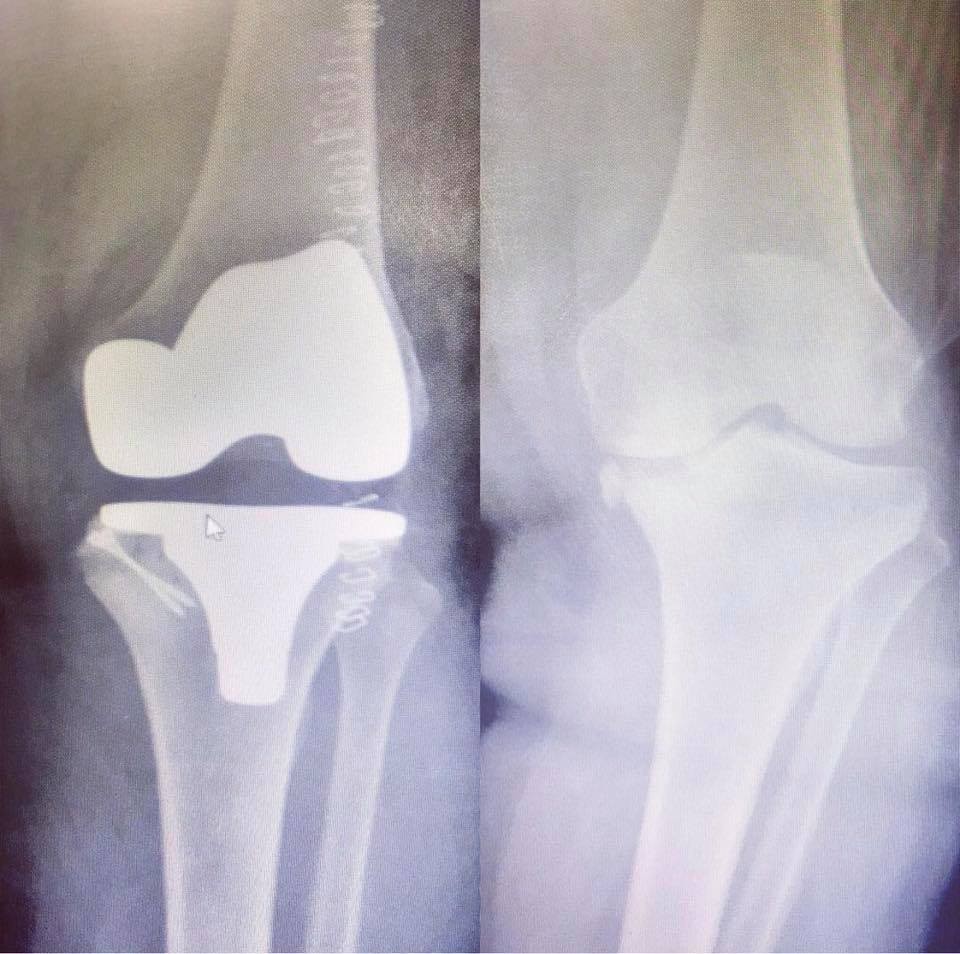

Diz kireçlenmesinde hastanın yaşına ve kireçlenmenin derecesine göre değişen tedavi modelleri uyguladıklarını da kaydeden Op. Dr. Mutlu Güngör, “Diz kireçlenmesi ilerleyici bir hastalıktır. Bu nedenle erken yakalanırsa ilerlemesi durdurulabilmekte, kıkırdaklar korunabilmekte ve tedavide başarıya gidilebilmektedir. Bu tedavi modellerinden bahsetmek gerekirse en basit yöntemle hastalarımıza kilo vermeyi ve egzersiz önermekteyiz. Ağrı kesici ilaçlar, jeller, dize uygulanan sıvı iğneleri, PRP (kendi kanından yapılan diz sıvısı) kök hücre tedavileri, diz protezi dediğimiz büyük cerrahilere kadar değişen tedavi yöntemleri mevcuttur” diyerek sağlıklı bir yaşam için herkesi öncelikle doğal ve dengeli beslenmeye, durumuna göre spor yapmaya ve başta sigara olmak üzere zararlı alışkanlıklardan uzak durmaya çağırdı.